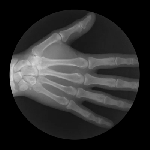

JOINTS IN MOTION

Cameron Drake of San Francisco has created a collection of magnificent images showing joints in motion. He was aided by orthopedic physician Dr. Noah Weiss and the finished product is completely amazing. If you’d like to know more about the project, please check out Drake’s blog.